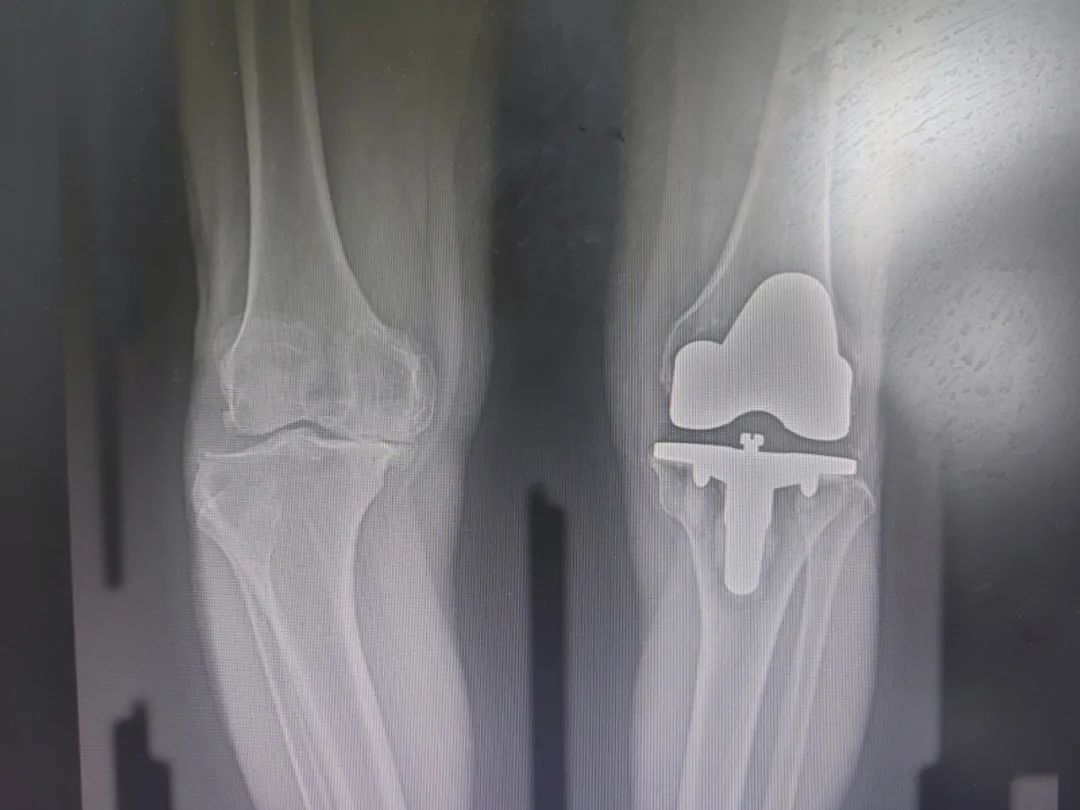

▲术前图

“患者大概3年前做的左膝关节置换术。当时右膝已经出现疼痛症状,近一个月内患者右膝关节反复疼痛,晨僵时间持续约30分钟,活动时有骨擦音。结合影像诊断,确诊为‘右侧膝关节骨性关节炎'。”骨科王怀波主任说。